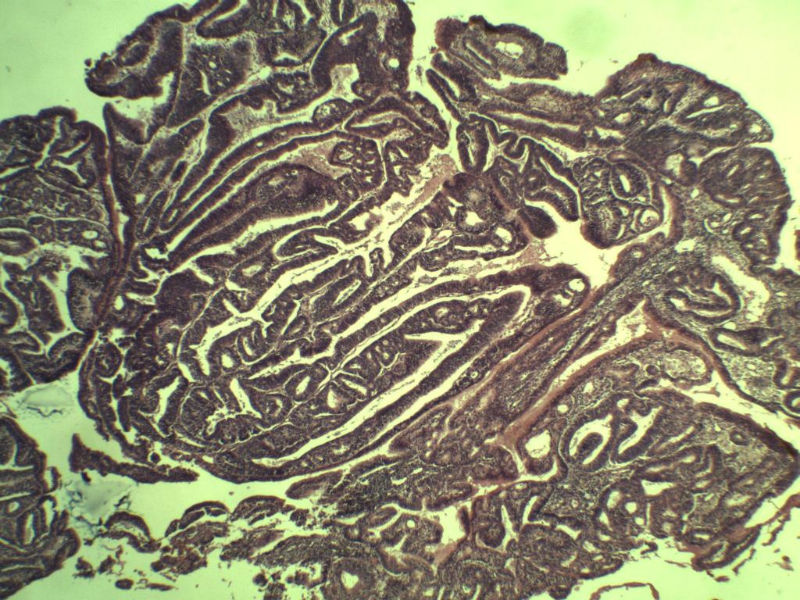

女 32岁 不规则阴道流血 一年  请各位老师看看 谢谢了

遵义医学院附属医院会诊结果    "复杂性增生伴非典型性 "

补充一下病史 病人10个月前因月经不规则行诊刮 诊断非典型性增生  上了曼月乐避孕环(好像是缓慢释放孕激素的那种),         都用激素治疗大半年了 还是这个样子 我还是觉得是癌  只有追踪一下以后病人的情况吧

高分化子宫内膜样癌

非典型复杂性子宫内膜增生,应了解雌孕激素情况。

子宫内膜复杂性非典型性增生,局灶区间质肉芽样(图5)及蜕膜样变,不够癌,建议临床查激素水平并追踪。

从照片看,没看到浸润的地方,我考虑是子宫内膜重度不典型增生。